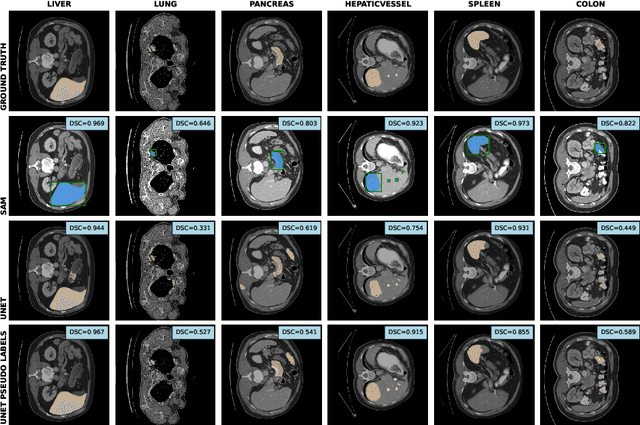

The field of medical image segmentation is hindered by the scarcity of large, publicly available annotated datasets. Not all datasets are made public for privacy reasons, and creating annotations for a large dataset is time-consuming and expensive, as it requires specialized expertise to accurately identify regions of interest (ROIs) within the images. To address these challenges, we evaluate the performance of the Segment Anything Model (SAM) as an annotation tool for medical data by using it to produce so-called "pseudo labels" on the Medical Segmentation Decathlon (MSD) computed tomography (CT) tasks. The pseudo labels are then used in place of ground truth labels to train a UNet model in a weakly-supervised manner. We experiment with different prompt types on SAM and find that the bounding box prompt is a simple yet effective method for generating pseudo labels. This method allows us to develop a weakly-supervised model that performs comparably to a fully supervised model.